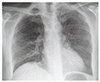

胸壁穿通性膿胸

Empyema Necessitans

66 歳の男性が,2 週間前から続く息切れと咳嗽,5 日前から続く左側腹部痛,2 日前に左背側に出現した急速に拡大する腫瘤を訴えて受診した.